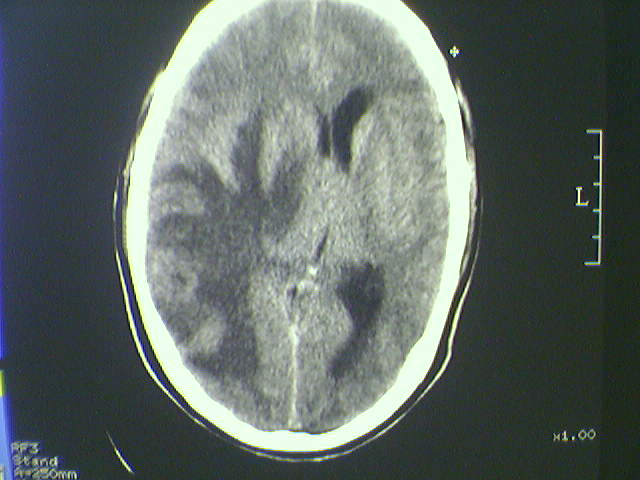

标题: CT21792:男48岁,头痛昏一月加重伴双下肢无力一天,反应迟 [打印本页]

标题: CT21792:男48岁,头痛昏一月加重伴双下肢无力一天,反应迟

病史不详;支持脑转移瘤诊断。

支持脑转移瘤诊断。

多发转移瘤

水肿占位效应明显,支持脑转移瘤诊断

支持 多发性脑转移瘤。